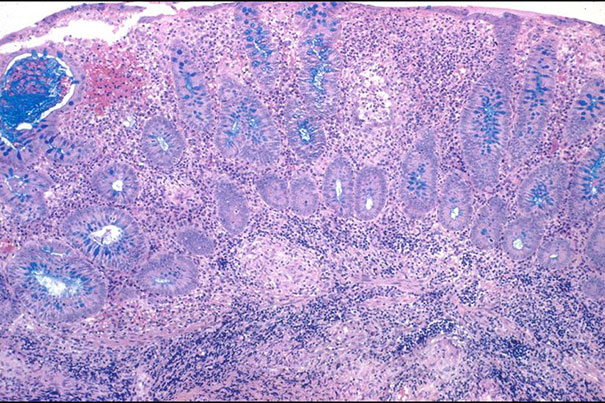

Human-gut-on-a-chip model offers hope for IBD sufferers

In a new study, the Wyss Institute’s human-gut-on-a-chip technology is used to co-culture gut microbiome and human intestinal cells, which could spur innovation of novel therapies for inflammatory bowel diseases.